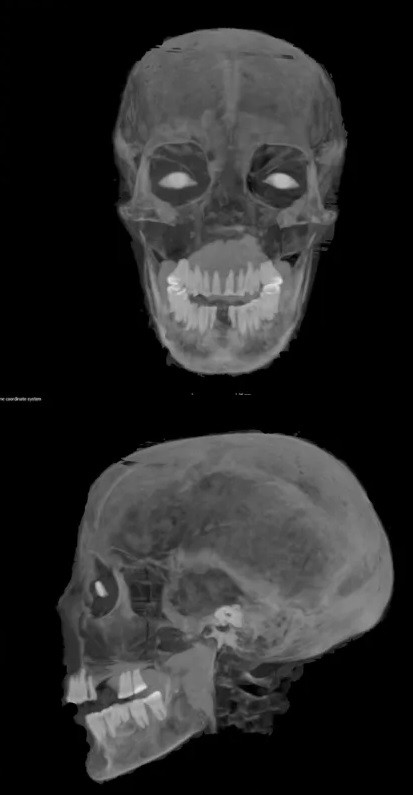

Ảnh chụp CT cũng hé lộ nhiều chi tiết mới về sức khỏe của quý bà Chenet-aa trong những ngày cuối đời. Nữ quý tộc qua đời ở cuối tuổi 30 hoặc đầu tuổi 40 nhưng chưa thể xác định nguyên nhân tử vong của bà.

Hàm răng của quý bà Chenet-aa không ở tình trạng tốt khi nhiều chiếc bị mất khi chết trong khi số răng còn lại có dấu hiệu bị mài mòn. Các chuyên gia cho rằng điều này liên quan đến chế độ ăn uống có hại cho men răng của bà.

Giới chuyên gia cũng phát hiện xác ướp của quý bà Chenet-aa có đặt đôi mắt nhân tạo ở hốc mắt để giúp bà có thể nhìn được ở thế giới bên kia. Ảnh: The Field Museum.